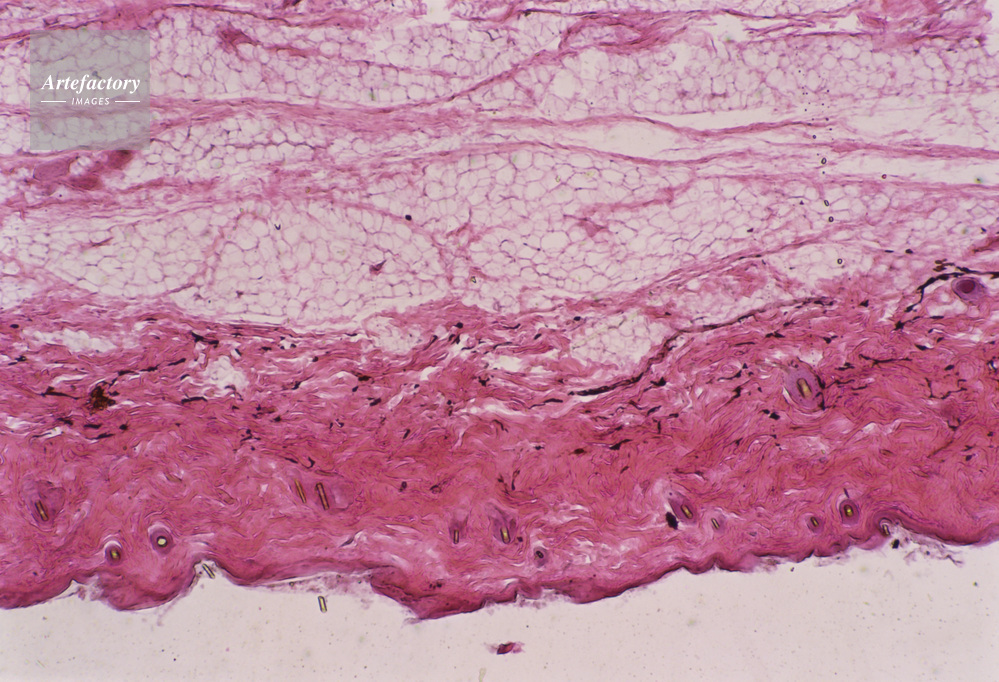

| 作品タイトル | 顕微鏡写真 | モデルリリース | なし | |

| キャプション | 皮膚,猿,20倍 | 制限事項 | ||